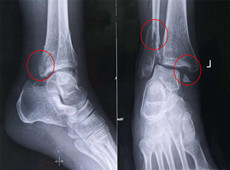

【醫(yī)療科普】踝關(guān)節(jié)骨折的主要類型及其影像學(xué)表現(xiàn)

大家好,我是南京醫(yī)科大學(xué)第二附屬醫(yī)院骨科副主任醫(yī)師王伯堯,從事骨科臨床工作十余年,擁有豐富的骨科臨床經(jīng)驗(yàn),主要研究方向?yàn)楣强剖中g(shù)機(jī)器人的開發(fā)與臨床應(yīng)用,今天跟大家介紹踝關(guān)節(jié)骨折的幾種常見類型及其在X影像上的表現(xiàn)。接下來跟...